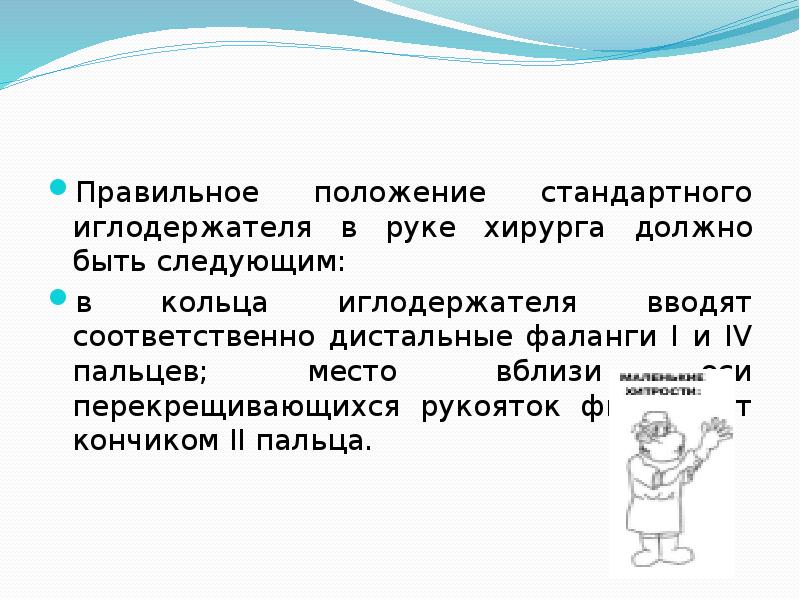

- 9. Правильное положение стандартного иглодержателя в руке хирурга должно быть следующим: